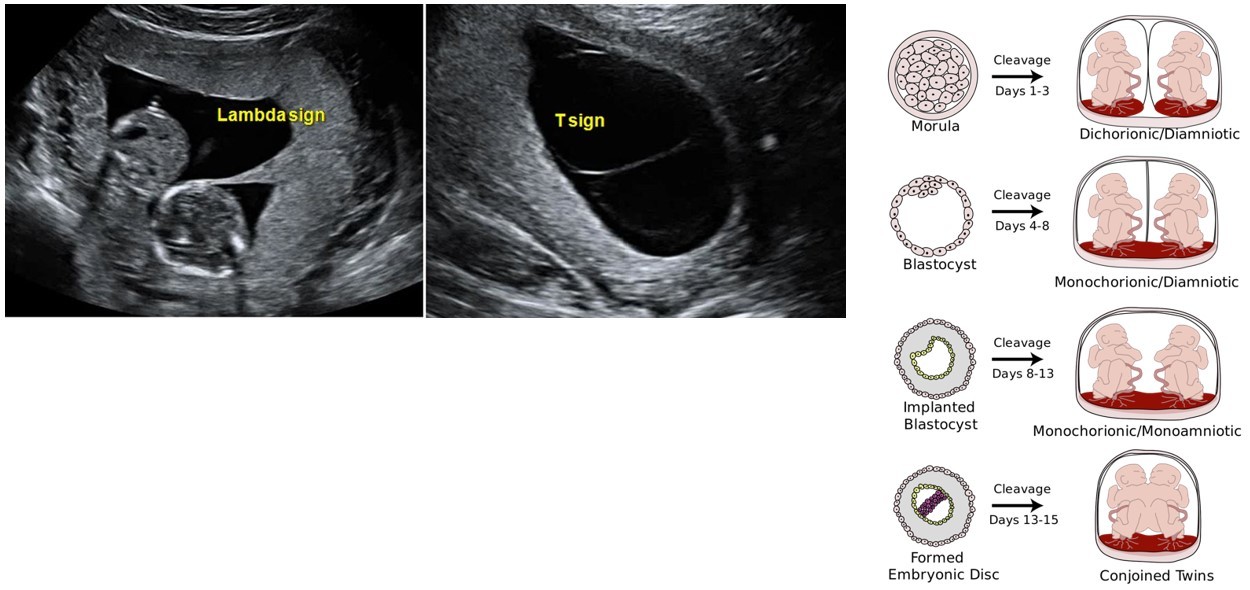

• Split 0-4 days → dichorionic diamniotic → 2 placenta and 2 amniotic sacs (25%)

• S/S: λ sign (triangular placental tissue projection into base of membranes)

• Split 4-8 days → monochorionic diamniotic → 1 placenta and 2 amniotic sacs (75%)

• S/S: T-sign (no placental tissue projection into base of membranes)

• Split 8-12 days → monochorionic monoamniotic → 1 placenta and 1 amniotic sac (1%)

• S/S: T-sign, ‘entangled cords’

• Split >12 days → conjoined twins (<1%)